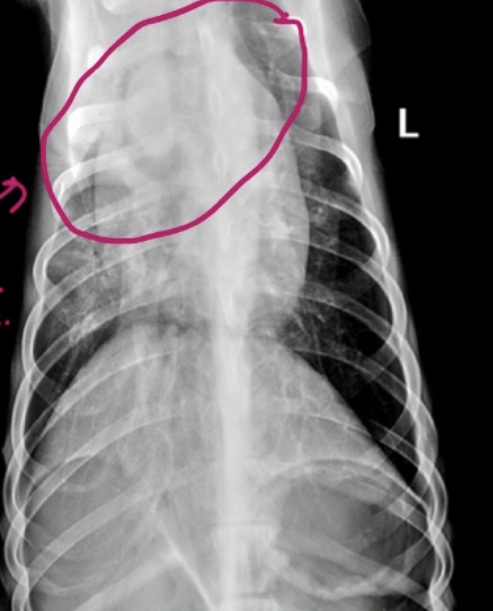

What finding is circled here?

A

Air bronchogram